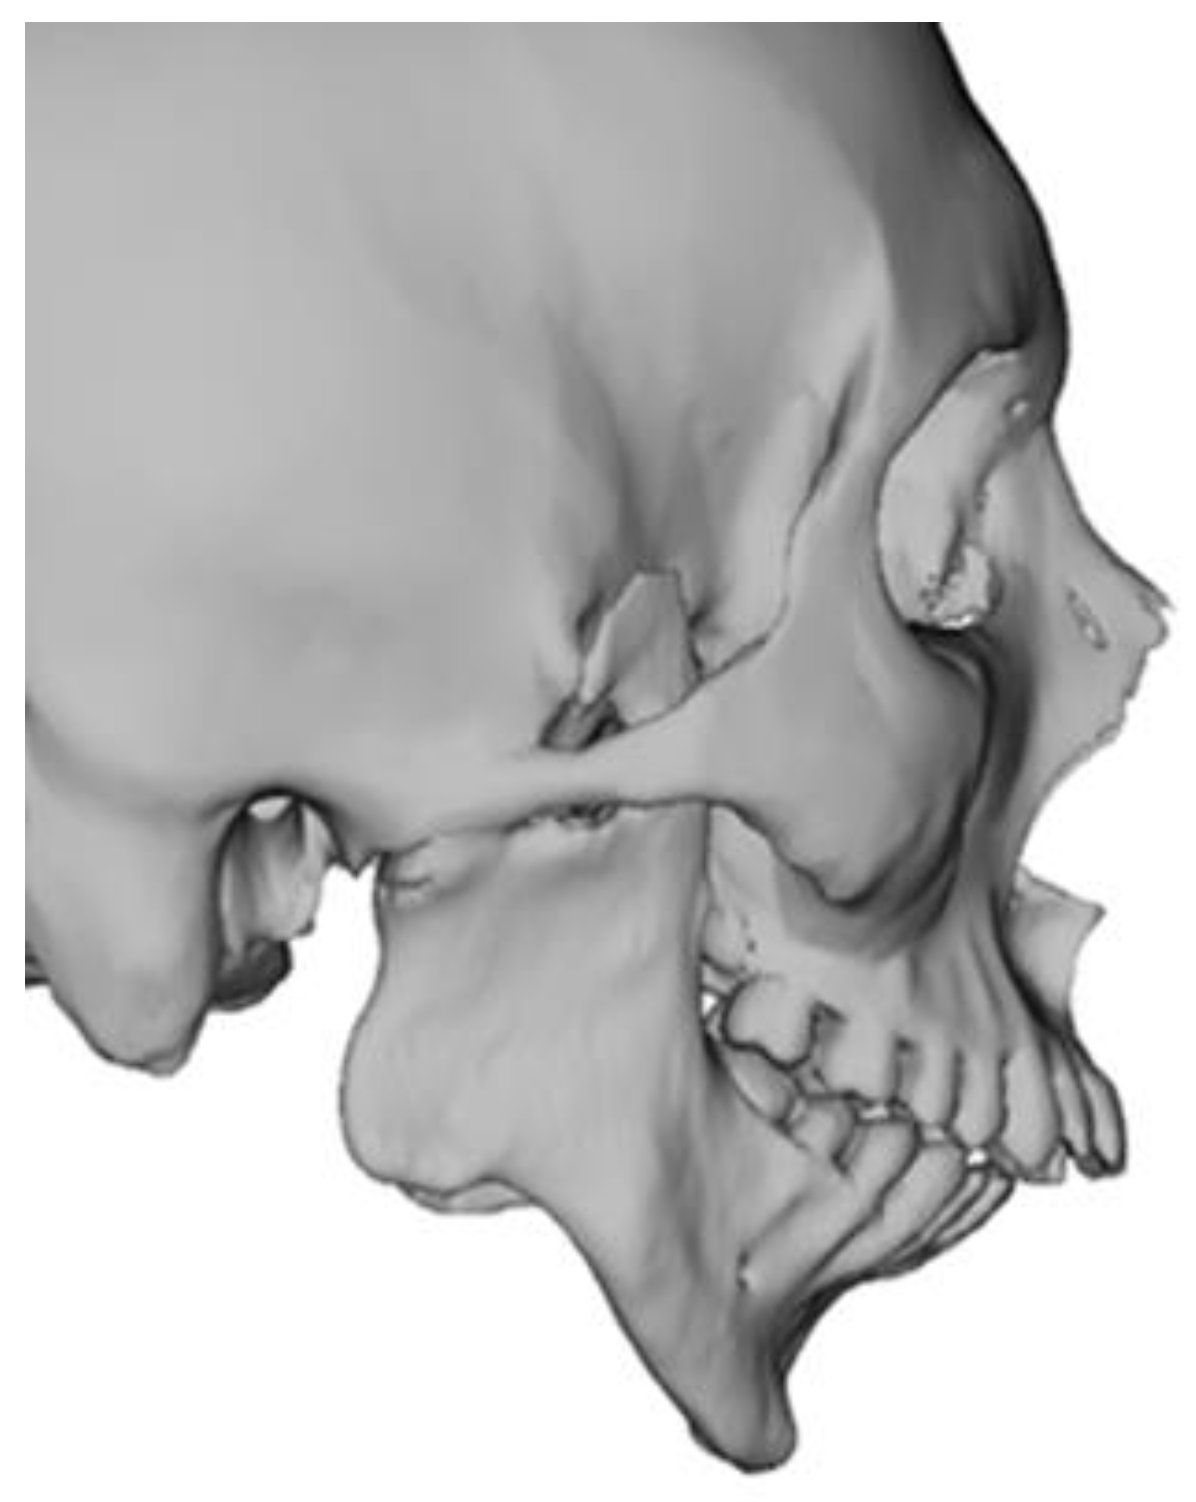

2.2. Virtual Surgical Planning and Computer-Aided Manufacturing Workflow

2.3. Surgical Technique

2.3.1. Mandible